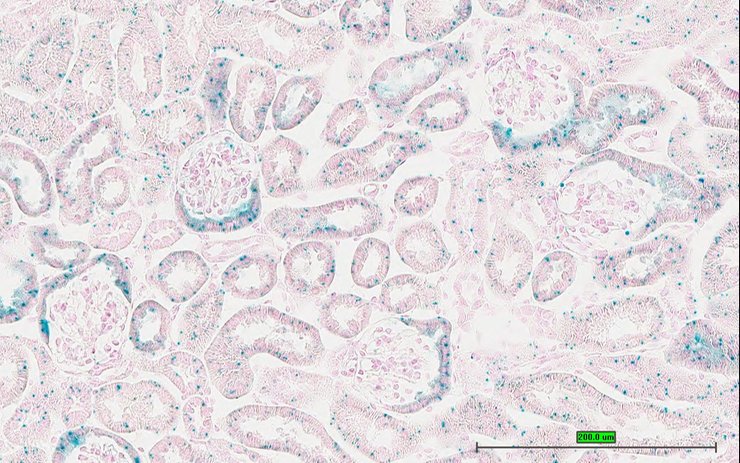

Specimen UC Davis_1882229: postnatal adult; Nfil3tm1.1(KOMP)Vlcg/Nfil3+ (more )

Structure Level Pattern Image Note

TS28: metanephros Present UC Davis_1882229 kidney

Specimen UC Davis_1882230: postnatal adult; Nfil3tm1.1(KOMP)Vlcg/Nfil3+ (more )

TS28: metanephros Present UC Davis_1882230 kidney

TS28: metanephros Present UC Davis_1882302 kidney

Specimen UC Davis_1882303: postnatal adult; Nfil3tm1.1(KOMP)Vlcg/Nfil3+ (more )

TS28: metanephros Present UC Davis_1882303 kidney